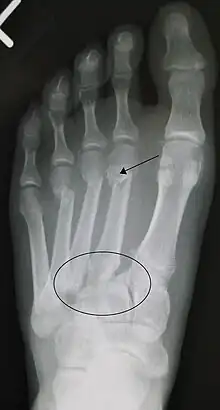

| An X-ray of a Lisfranc injury | |

In a high energy injury to the midfoot, such as a fall from a height or a motor vehicle accident, the diagnosis of a Lisfranc injury should, in theory at least, pose less of a challenge. There will be deformity of the midfoot and X-ray abnormalities should be obvious. Further, the nature of the injury will create heightened clinical suspicion and there may even be disruption of the overlying skin and compromise of the blood supply. Typical X-ray findings would include a gap between the base of the first and second toes.[8] The diagnosis becomes more challenging in the case of low energy incidents, such as might occur with a twisting injury on the racquetball court, or when an American Football lineman is forced back upon a foot that is already in a fully plantar flexed position. Then, there may only be complaint of inability to bear weight and some mild swelling of the forefoot or midfoot. Bruising of the arch has been described as diagnostic in these circumstances but may well be absent.[9] Typically, conventional radiography of the foot is utilized with standard non-weight bearing views, supplemented by weight bearing views which may demonstrate widening of the interval between the first and second toes, if the initial views fail to show abnormality. Unfortunately, radiographs in such circumstances have a sensitivity of 50% when non-weight bearing and 85% when weight bearing, meaning that they will appear normal in 15% of cases where a Lisfranc injury actually exists.[10] In the case of apparently normal x-rays, if clinical suspicion remains, advanced imaging such as magnetic resonance imaging (MRI) or computed tomography (CT scan) is a logical next step.[11]